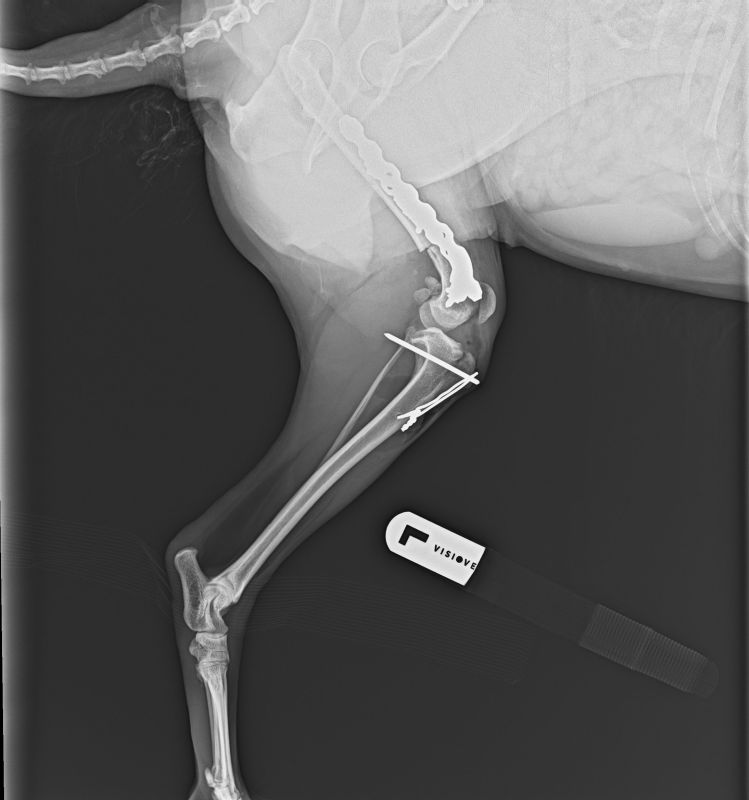

Als Masha aufgefunden wurde, konnte sie mit den Hinterbeinen kaum richtig stehen, geschweige denn laufen.

Masha wurde in der Tierklinik vorgestellt und es wurde beidseitig starke Patellaluxation diagnostiziert und die Knochen und Muskeln waren deformiert. Sie hatte sicher höllische Schmerzen.

Mashas rechtes Knie konnte am 26.November 2024 erfolgreich operiert werden.

Am 11.3.2025 konnte in der Klinik auch noch die linke Seite erfolgreich operiert werden. Das Video beweist, dass sie jetzt schon viel besser läuft und begonnen hat, das Leben wieder zu geniessen.